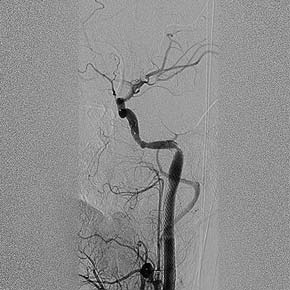

При повторной явке через 4 и 9 мес пациент никаких жалоб не предъявляет. Двигательная активность в конечностях в полном объёме, сенсомоторной афазии нет. Самочувствие хорошее. Уровень активности умеренный (занимается лёгкой атлетикой 3 раза в неделю по 60 мин). При контрольной цереброангиографии патологии не выявлено, контуры стентов ровные, рестенозы и диссекции не визуализируются (рис. 5–7).

Рис. 7. Контрольная цереброангиография через 9 мес. Стенты функционируют нормально